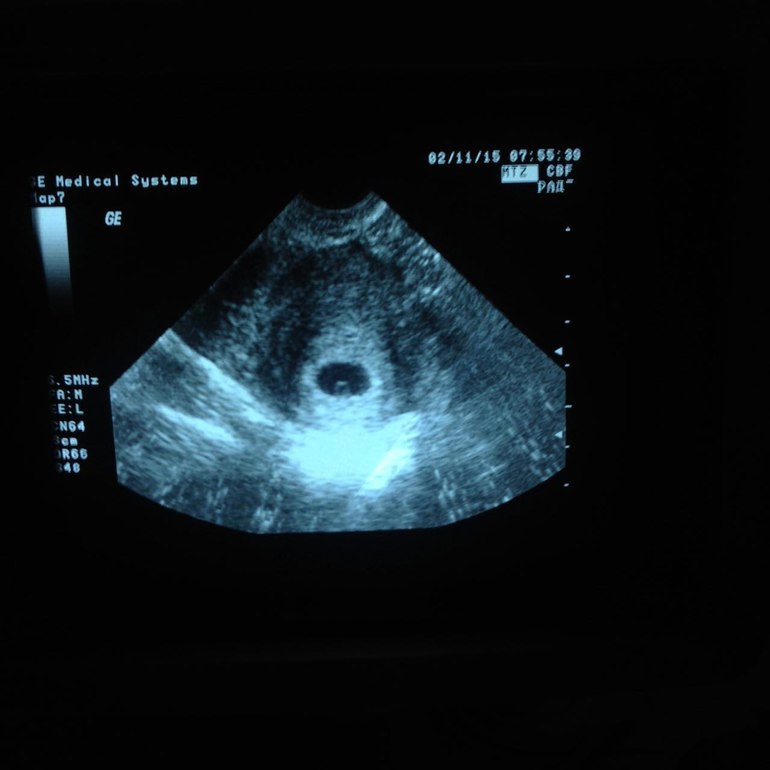

Через 14 дней после ЭКО проводится тест на ХГЧ, с помощью которого определяется факт наступления беременности. В случае успешного зачатия женщины проходят первое УЗИ уже на 5-й неделе гестации.

В среднеэмбриональный период плод находится возле стенки желточного мешка, который с помощью УЗИ визуализируется как небольшая киста сферической формы с плодным яйцом внутри. Зародыш располагается внутри мешка эксцентрично, из-за чего на мониторе возникает типичная УЗ-картина «двойного пузыря».

5 неделя беременности соответствует началу второго акушерского месяца, т.е. с момента имплантации плодного яйца в эндометрий проходит около 29-35 дней. На ультразвуковом фото 5-недельный эмбрион имеет вид небольшого цилиндра протяженностью 6-7 мм. В этот период беременности можно различить зачатки рук и ног, а также ушные раковины и носовые щели зародыша.